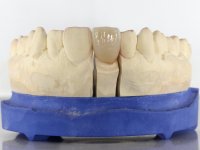

It was proposed to the patient to make a full-coated crown with a ceramic-coated Zr infrastructure that would aesthetically and functionally rehabilitate tooth 11. We decided not to redo the endodontic treatment given the absence of signs and symptoms for more than 20 years. The coronary structure would be previously reinforced with the placement of an intraradicular post and the making of a new restoration in composite resin. Periodontal pocket would be surgically addressed.

The treatment began with the placement of an intraradicular post and the creation of a new composite resin restoration. This procedure was performed with a surgical approach that allowed the remaining margins to be completely exposed, which were shown to be at a very infra-gingival level. Simultaneously, the periodontal pocket was curetted and root scaling and root planning of adjacent teeth were performed. Two months after this first intervention, the making of the crown began. A pre-print on silicone was performed to make a temporary crown with dual-cured composite resin. Gingival retraction was performed using the technique of kaolin paste compressed by the provisional crown. The impression was made using the double-mix technique with double viscosity with quick-setting silicone. In the laboratory, a crown with a ceramic-coated Zr infrastructure was made. The crown slightly overlapped tooth 12, allowing a dimensionally mimicry of the symmetrical tooth. Its fit was confirmed and approved by the patient; it was definitively cemented with resin-reinforced glass ionomer cement.